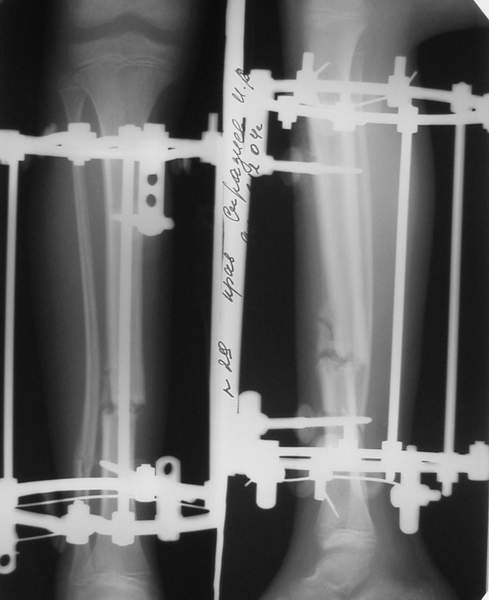

3a

3b

3c

В аттачте № 3 - один из примеров полукольцевого аппарат...

Это уже я баловался.

Итог? Работы больше (по времени и

интраоп "подгонке"), срастается также, а особого преимущества по сравнению с

"чиста" кольцевым (вес, удобство ношения и пр.) - я, по крайней мере,

не нашел.

Теперь не балуюсь.

Может быть зря?